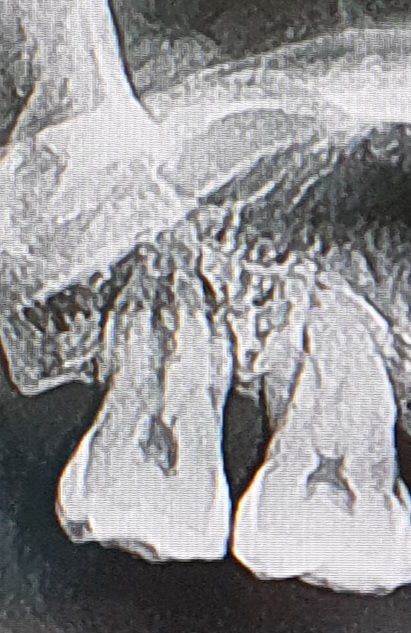

아랫니 발치하다가 발치기구에 오른쪽 맨끝치아를 세게 부딪혔었어요.2주후 사진입니다.

부딪히고 나서 2주후에 치간칫솔에 찔려서 그런건지 잇몸염증으로 병원에 갔을때 찍은 사진입니다.

금이 간것은 없는지 살펴봐주세요.

하지만 사진으로 봤을 경우 치아에 뿌리 끝에 방사선 음영이 보이는 걸로 보여 염증이 있는 것으로 보입니다.

염증의 원인은 여러 가지 원인이 있을 수 있기 때문에 원인을 제거하는 것이 좋으며 치아 뿌리 쪽에 금이 가서 생긴 병소라면 치아를 발치를 해여할 수도 있습니다.

치아가 발치기구에 부딪혀서 흔들린다면 상당한 충격을 받은거 같습니다. 엑스레이 상으로는 금이간것처럼 보이진 않습니다. 일단은 1-2주 정도 지켜보시는게 좋을것같습니다.

다만 발치 중 과도한 동작으로 인접치아가 심하게 깨지거나 금이갔고 시린 증상 등이 있는 경우 추가적인 치료(신경치료, 크라운) 등을 해보고 그래도 안되면 빼야할 수도 있습니다 사진상으로는 크게 깨진 부위는 없고 금이갔는지 여부는 해상도가 좀 더 좋은 작은 사진을 찍어봐야 합니다